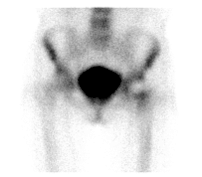

病例七:股骨头坏死

女性,33岁,因特发性血小板减少,长期服用类固醇激素治疗,近一个月来出现两侧髋关节酸痛。

d-spect怎么检查【核医学科普】SPECT-CT全身骨显像wholebody bone scan给全身骨骼拍张“艺术照”_https://www.jmylbn.com_新闻资讯_第26张

d-spect怎么检查【核医学科普】SPECT-CT全身骨显像wholebody bone scan给全身骨骼拍张“艺术照”_https://www.jmylbn.com_新闻资讯_第27张